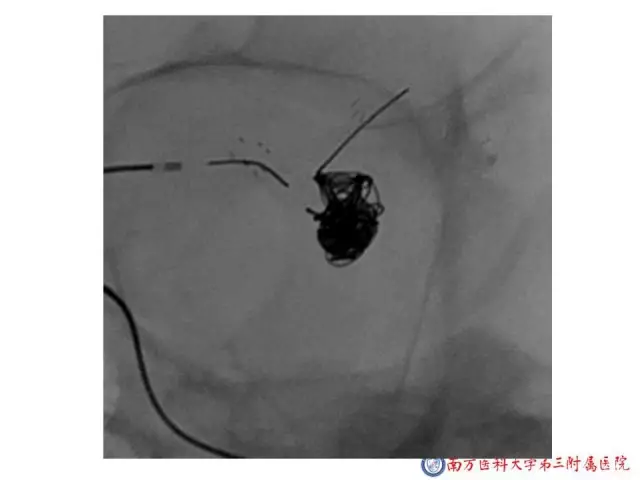

今天为大家分享的是“强生医疗CNV-神经介入专栏”第二十五期,由南方医科大学第三附属医院神经外科主任黄理金教授带来的“Enterprise支架辅助栓塞动脉瘤的优势”精彩讲课视频及PPT,欢迎观看。文章仅代表作者个人观点,如有不同见解,欢迎同道斧正!